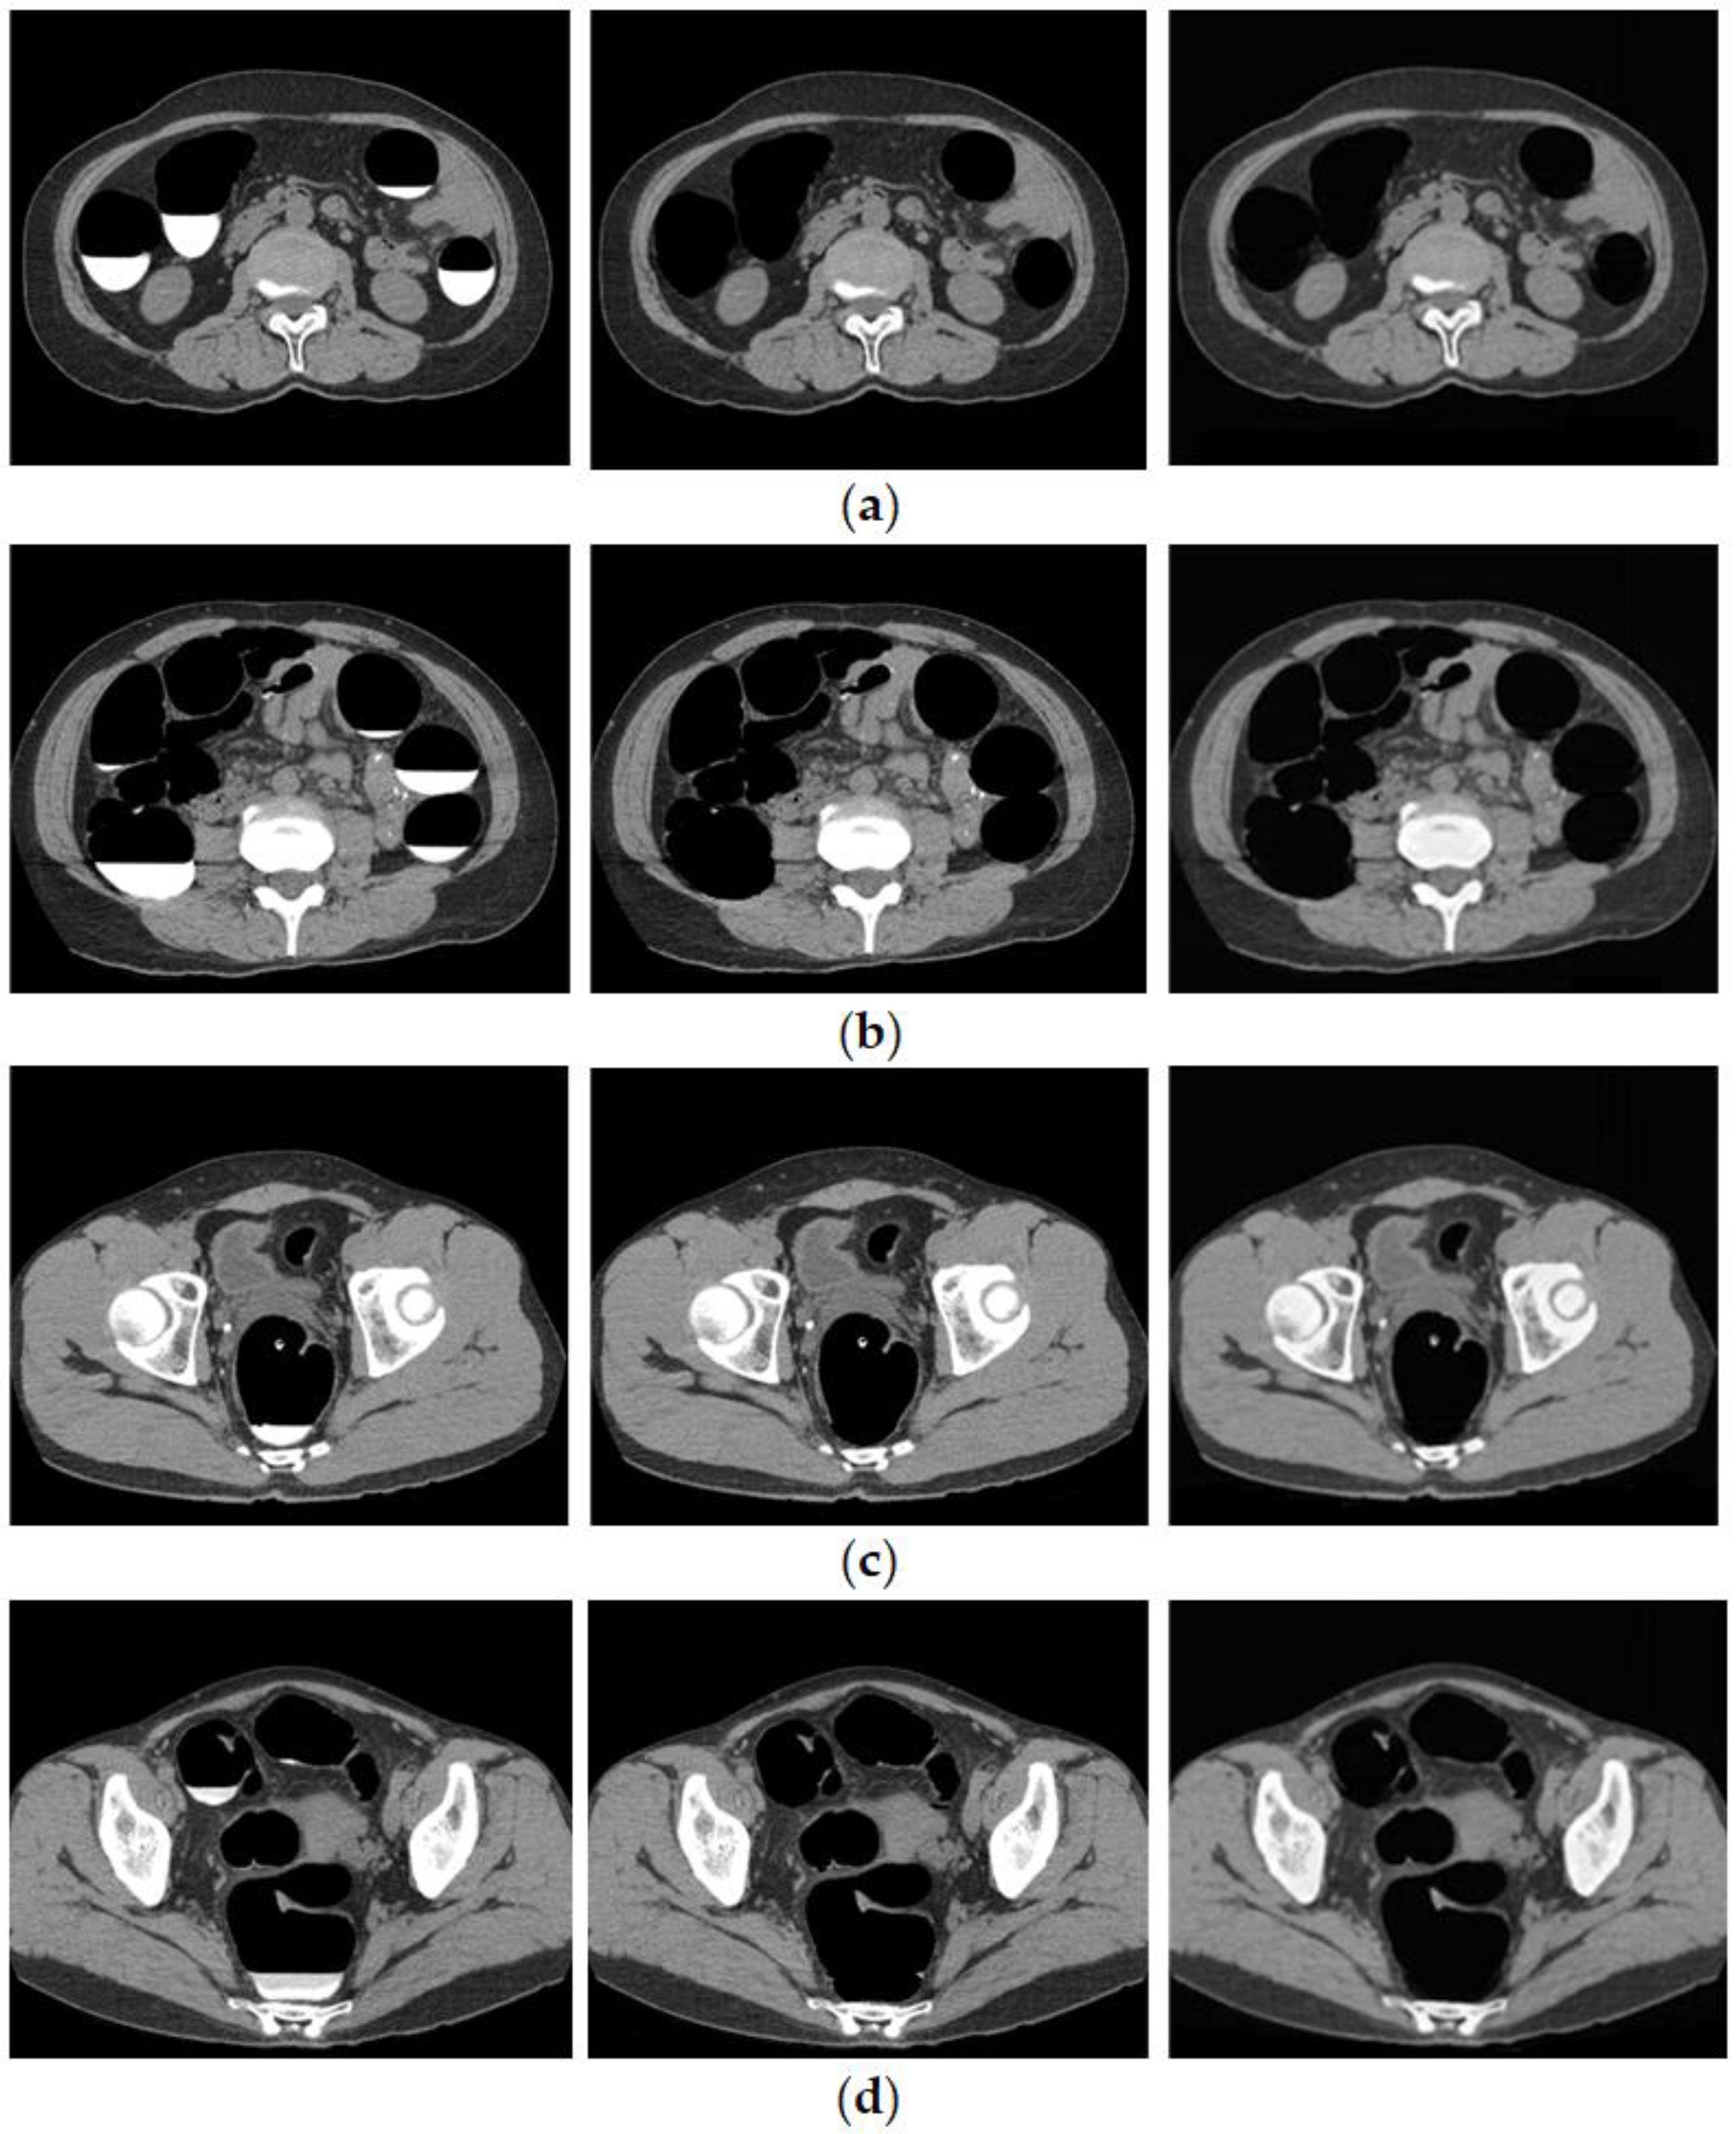

3.1. Cleansing Images Generated Using CycleGAN

4.1. Images Generated by CycleGAN